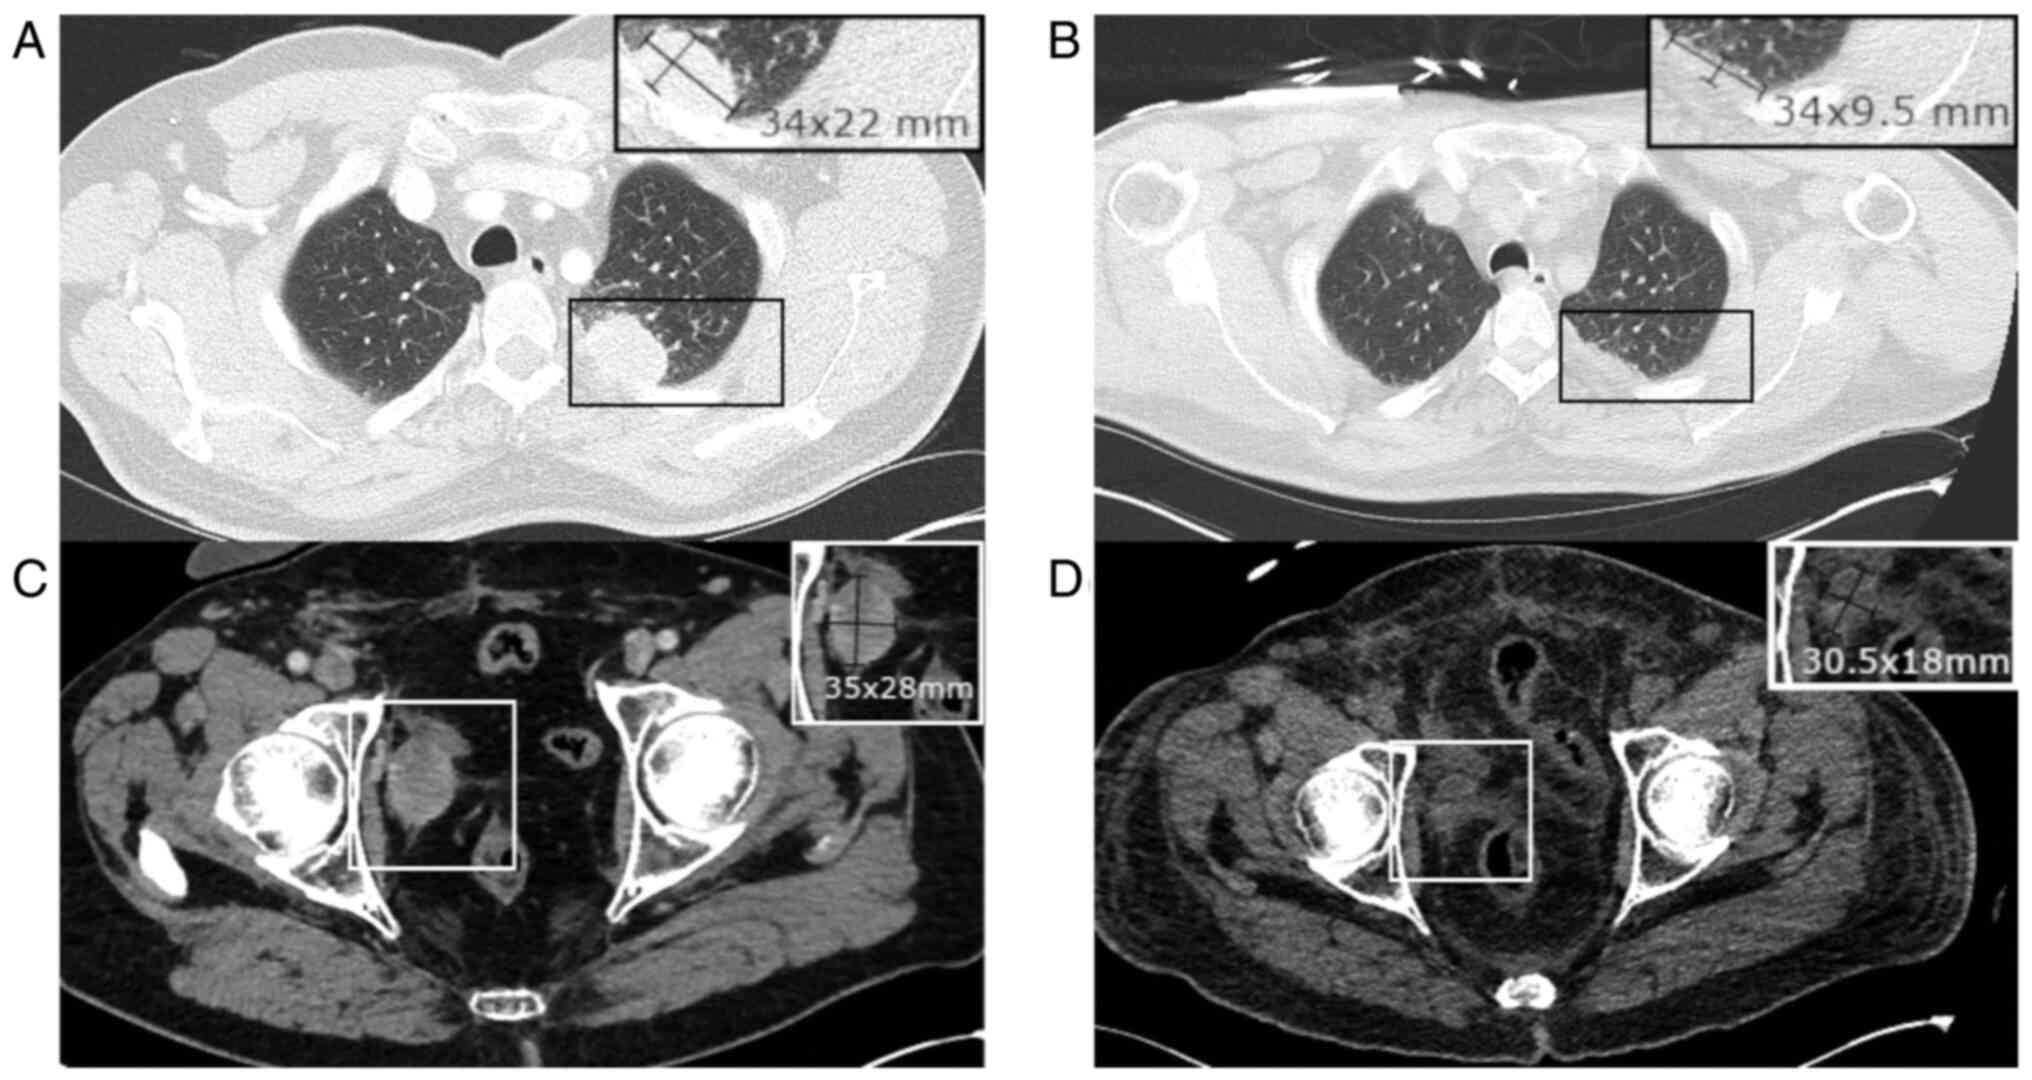

A thoraco-abdominal scan ruled out infection but revealed marked regression in known pelvic adenopathies and pulmonary metastases compared with a previous scan before EV treatment initiation (Fig. 2). This robust response to EV treatment supported its therapeutic effectiveness.

Figure 2

Comparison of pre-EV treatment (left) and post-EV treatment (right) scans, showing partial remission 18 days after initiation of treatment. (A) Lung metastasis: 34x22 mm. (B) Same lung metastasis after EV: 34x9.5 mm. (C) Mesorectal lymphadenopathy: 35x28 mm. (D) Same lymphadenopathy after EV: 30.5x18 mm. Please note that images were taken at the same level, and the second scan was performed without contrast, as oncologic evaluation was not its primary purpose. EV, enfortumab vedotin.